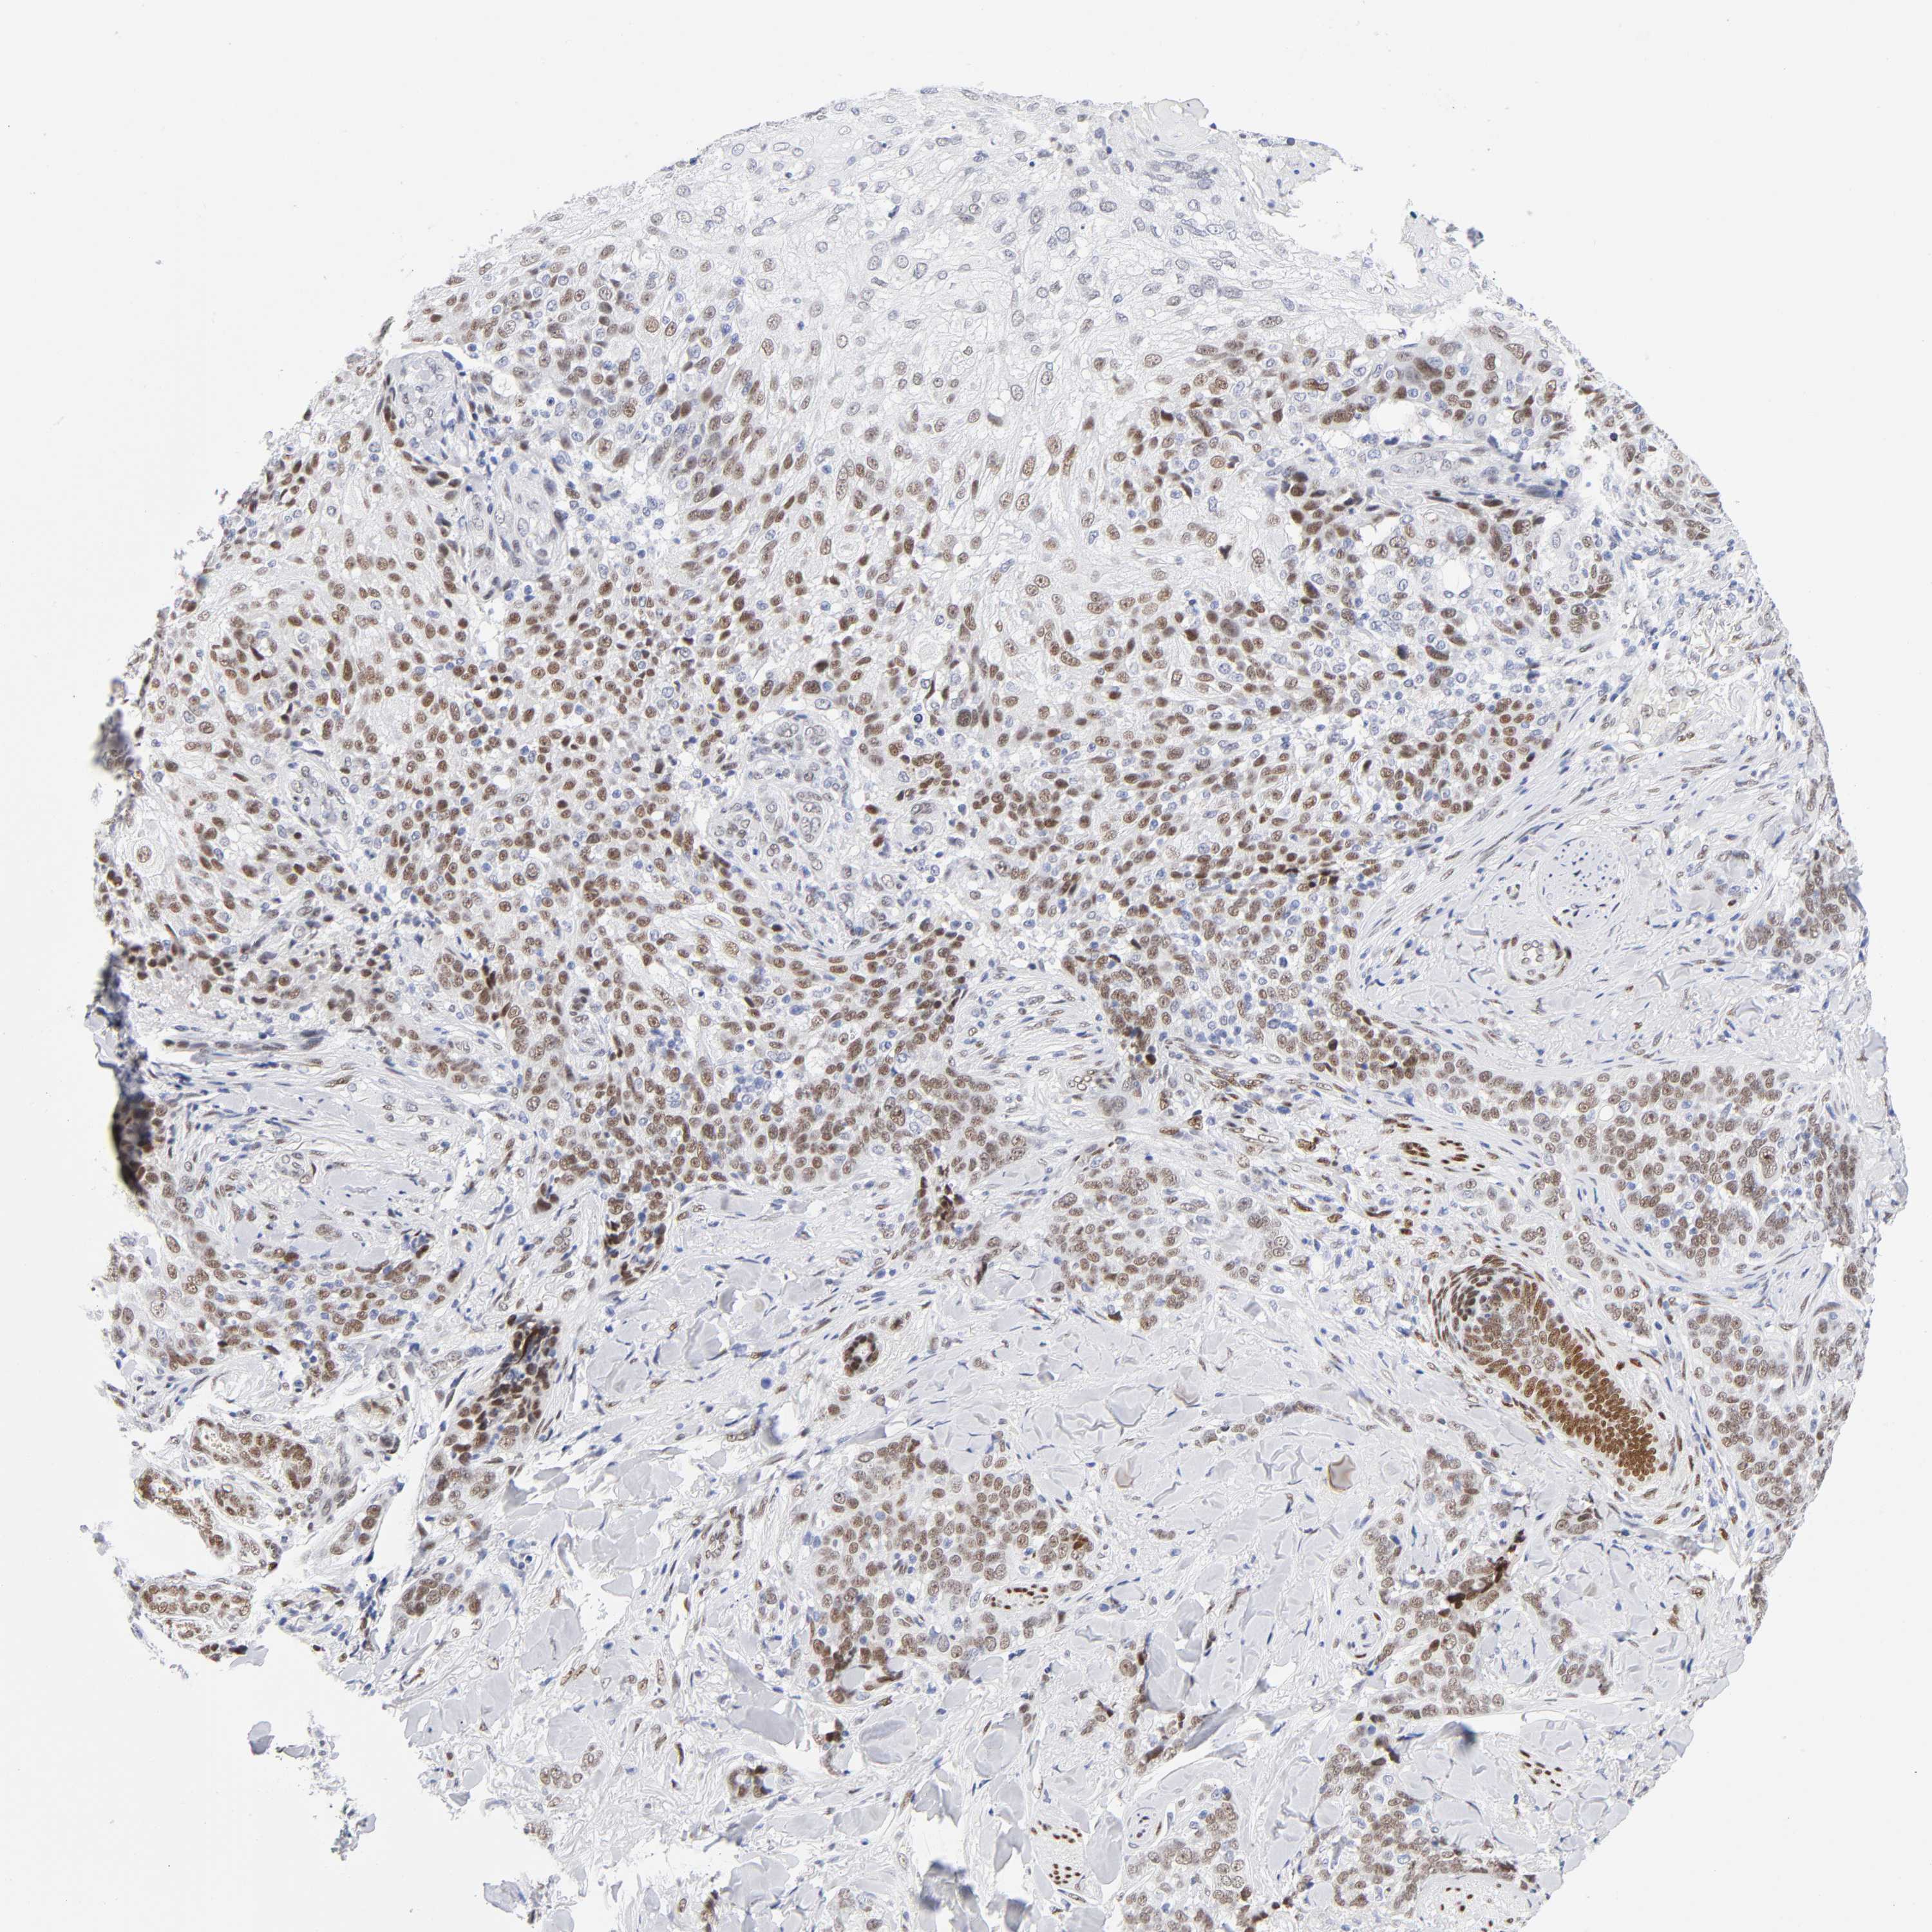

SKIN CANCER - Protein expressioni

A mouse-over function shows sample information and annotation data. Click on an image to view it in a full screen mode. Samples can be filtered based on level of antibody staining by selecting one or several of the following categories: high, medium, low and not detected. The assay and annotation is described here.

Antibody stainingi

Antibody staining in the annotated cell types in the current human tissue is reported as not detected, low, medium, or high, based on conventional immunohistochemistry profiling in selected tissues. This score is based on the combination of the staining intensity and fraction of stained cells.

Each image is clickable and will lead to virtual microscopy that enables deeper exploration of all samples and also displays staining intensity scores, fraction scores and subcellular localization as well as patient and tissue information for each sample.

Antibody CAB004674

Staining

High

Strong

>75%

Nuclear

Basal cell carcinoma

BCC, low aggressive